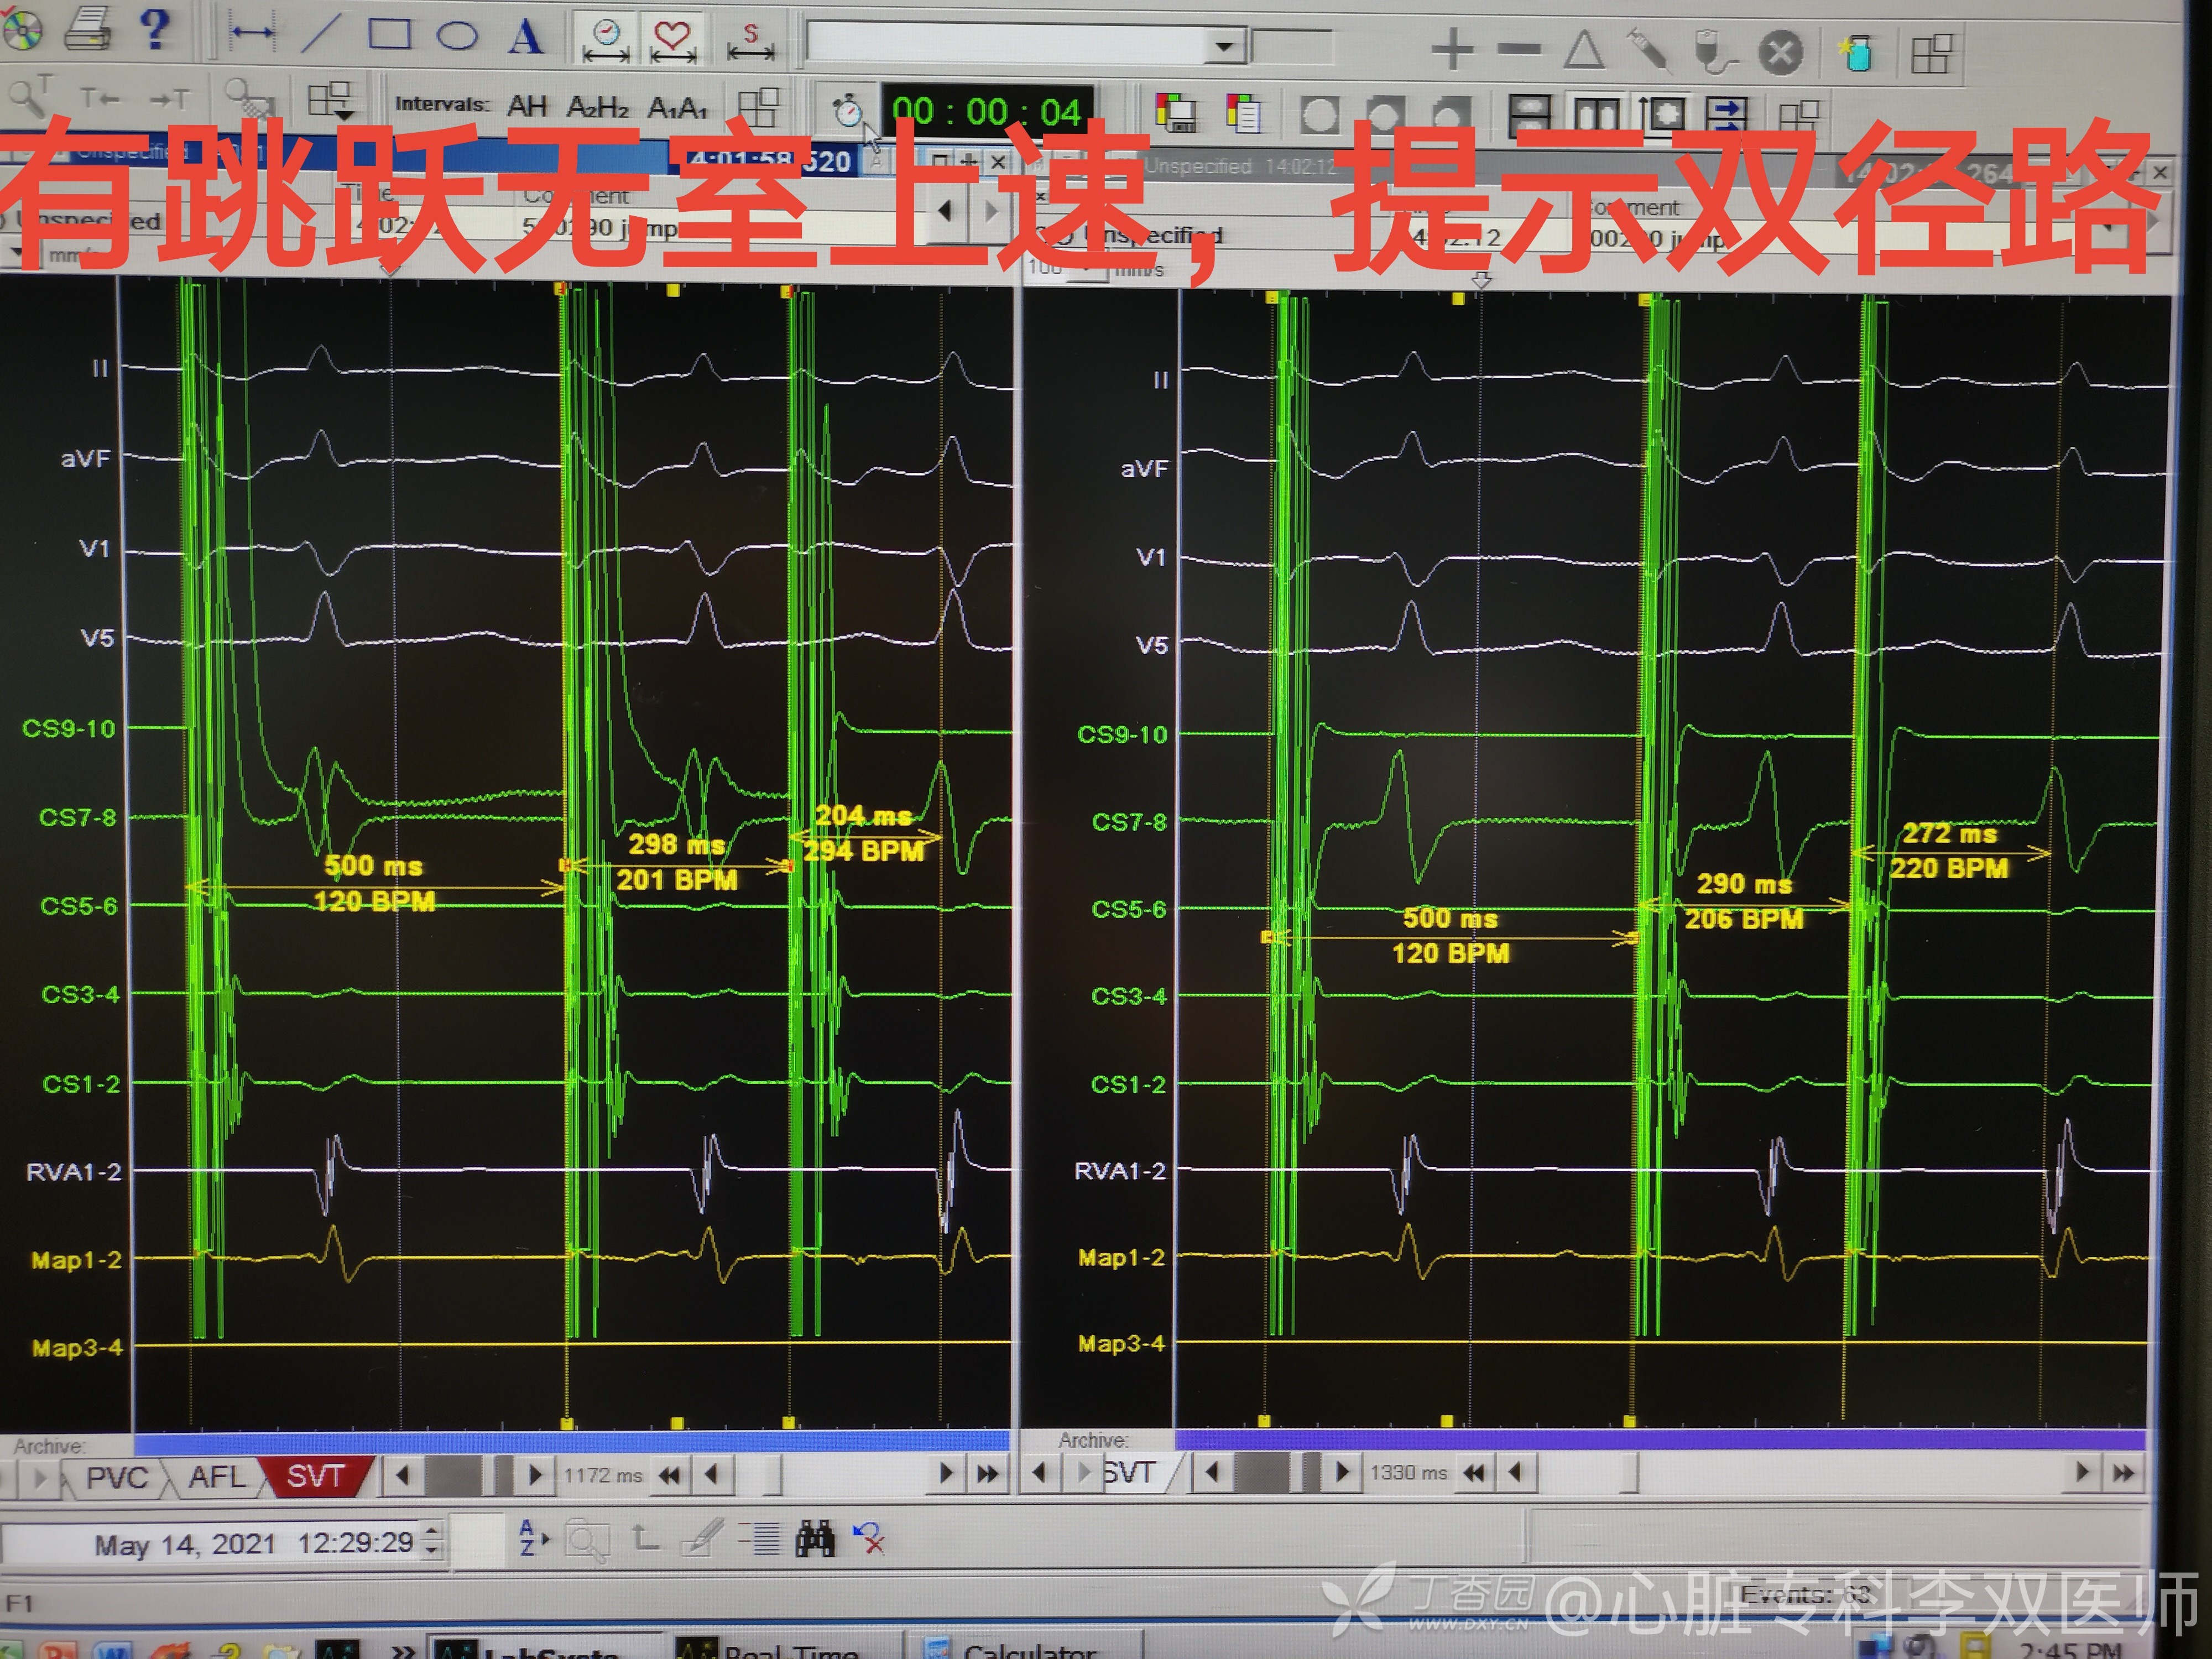

还有系统检查,果然!我们发现了同时存在“双径路”,很稳定诱发(S1S2,S1S2S3都是两次一样条件),但是没有回波,也不能诱发室上速。给了异丙肾反复刺激也是没有回波没有室上速,这种情况一般是不主张继续消融“双径路”的。

我们也收手了,不过乘着观察期间也去标了标右房三尖瓣环解剖图,中规中矩的形态,要消融双径路也预计难度不大!